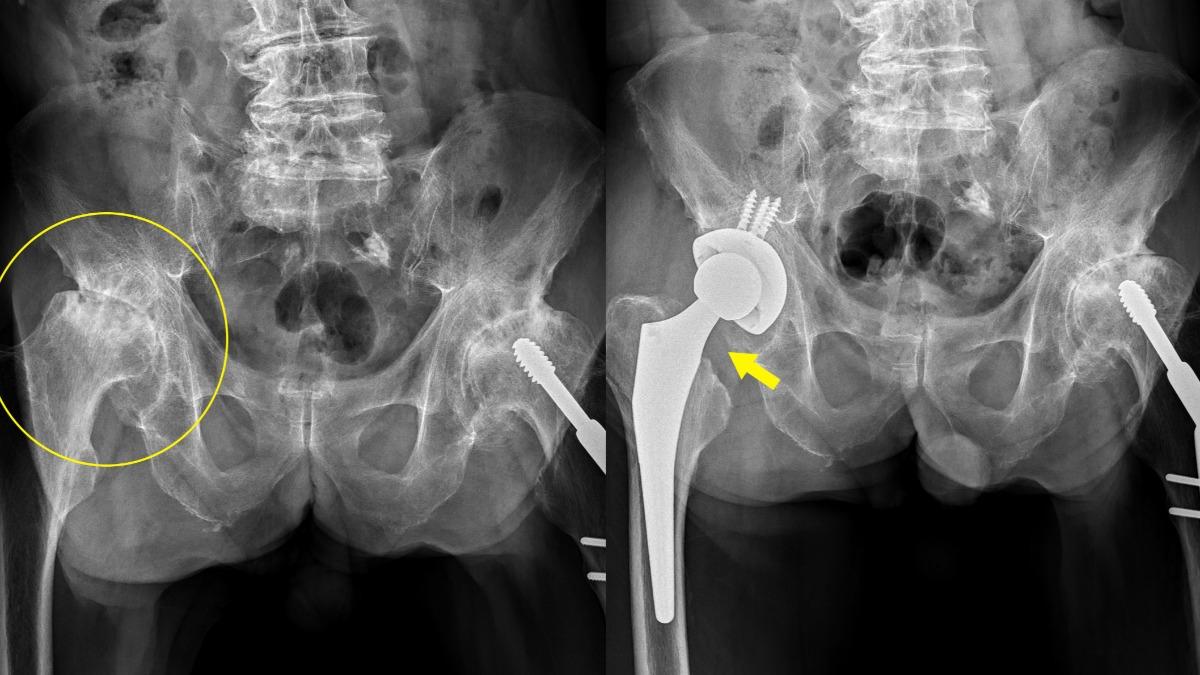

台中市一名74歲的施姓老翁,近年專注照顧重病臥床的母親,時刻協助頻繁翻身、抱起、扶重,即便身體出現腰與髖疼痛並延伸到鼠蹊部警訊,施翁也吃止痛藥硬撐,陪伴母親到最後一刻,不過因長久損傷,施翁髖關節軟骨幾乎消失、關節處骨頭黏在一起、股骨頭磨損到扁平狀,連站著都沒辦法,因此前往澄清醫院中港院區就診,骨科醫師洪舜奕也進行「人工全髖關節置換術」,目前施翁已修正長短腳問題,且能正常行走。